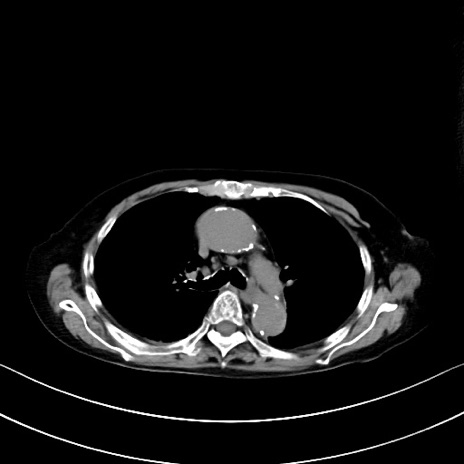

横断像